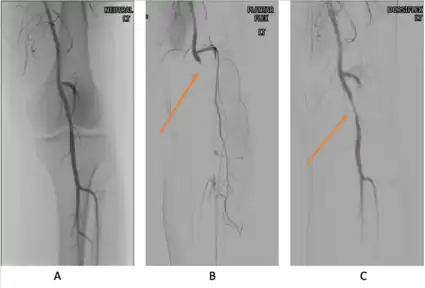

PAES should be suspected in young healthy male patients with clinical symptoms consistent with compression of the vascular structures and without significant cardiovascular risk factors such as smoking.[13] Multiple imaging modalities are used to confirm the diagnosis of PAES.[23] Based on a systemic review by Sinha et al, digital subtraction angiography (DSA) is the most common imaging used for PAES diagnosis, followed by ankle–brachial index (18 percent), computed tomography angiography (CTA) (12 percent), magnetic resonance angiography (MRA) (12 percent), duplex ultrasonography (DU) (10 percent), exercise ankle-brachial index (4 percent), and other modalities (4 percent).[23] According to a recent study by Willimas et al, a combination of DU and MRA is far superior in diagnosing PAES.[24]

Provocative maneuvers can be used to improve visualization of PAES on the imagines.[25] The patient is initially positioned supine with the legs straight, and then instructed to forcefully plantar-flex. A plantarflexion force of 0 to 70 percent maximum has been shown to maximize the sensitivity and specificity for PAES diagnosis.[25] The DU can be a quick, inexpensive, and noninvasive initial screening for PAES. Flow velocities in the popliteal artery will increase, as the popliteal artery is compressed, which is reflected on the DU. If DU is negative but there is still strong suspicion for PAES, MRA or CTA with provocative maneuvers are needed as follow-up imaging. MRA would demonstrate a focal occlusion or narrowing of the mid-popliteal artery, post-stenotic dilatation, or aneurysm of the distal popliteal artery. If MRA or CTA is[13] non-conclusive, DSA may be used as a further option with a high sensitivity (> 97%) for PAES diagnosis.[23]

Additionally, functional PAES in which the gastrocnemius hypertrophy causes arterial compression during exercise can be best evaluated with dynamic CT.[23] For dynamic CT, initial images are taken with the patient still. Further images are taken following a series of provocative maneuvers.